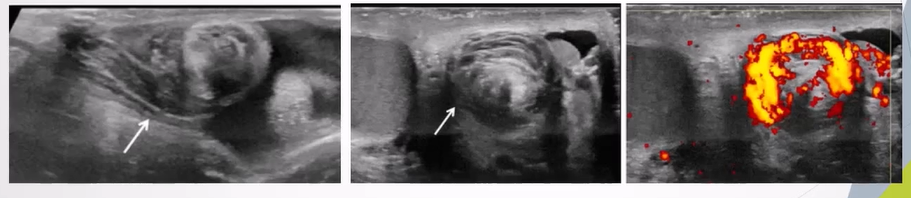

Twisting of Spermatic Cord:

Identified by the "whirlpool sign" indicating torsion.

Whirlpool sign - spiral twist in the spermatic cord seen in the external inguinal ring or in the scrotal sac.

Redundant Spermatic Cord:

Presence of excess and tortuous spermatic cord in the scrotal sac is a sign for the anomalous attachment of the tunica vaginalis

Bunched up cord appears as an ovoid heterogeneous mass with excessive twisting.

Can appear to include dilated anaechoic tubules representing congested vessels within the knot or mass

Can still have flow withn if partially twisted